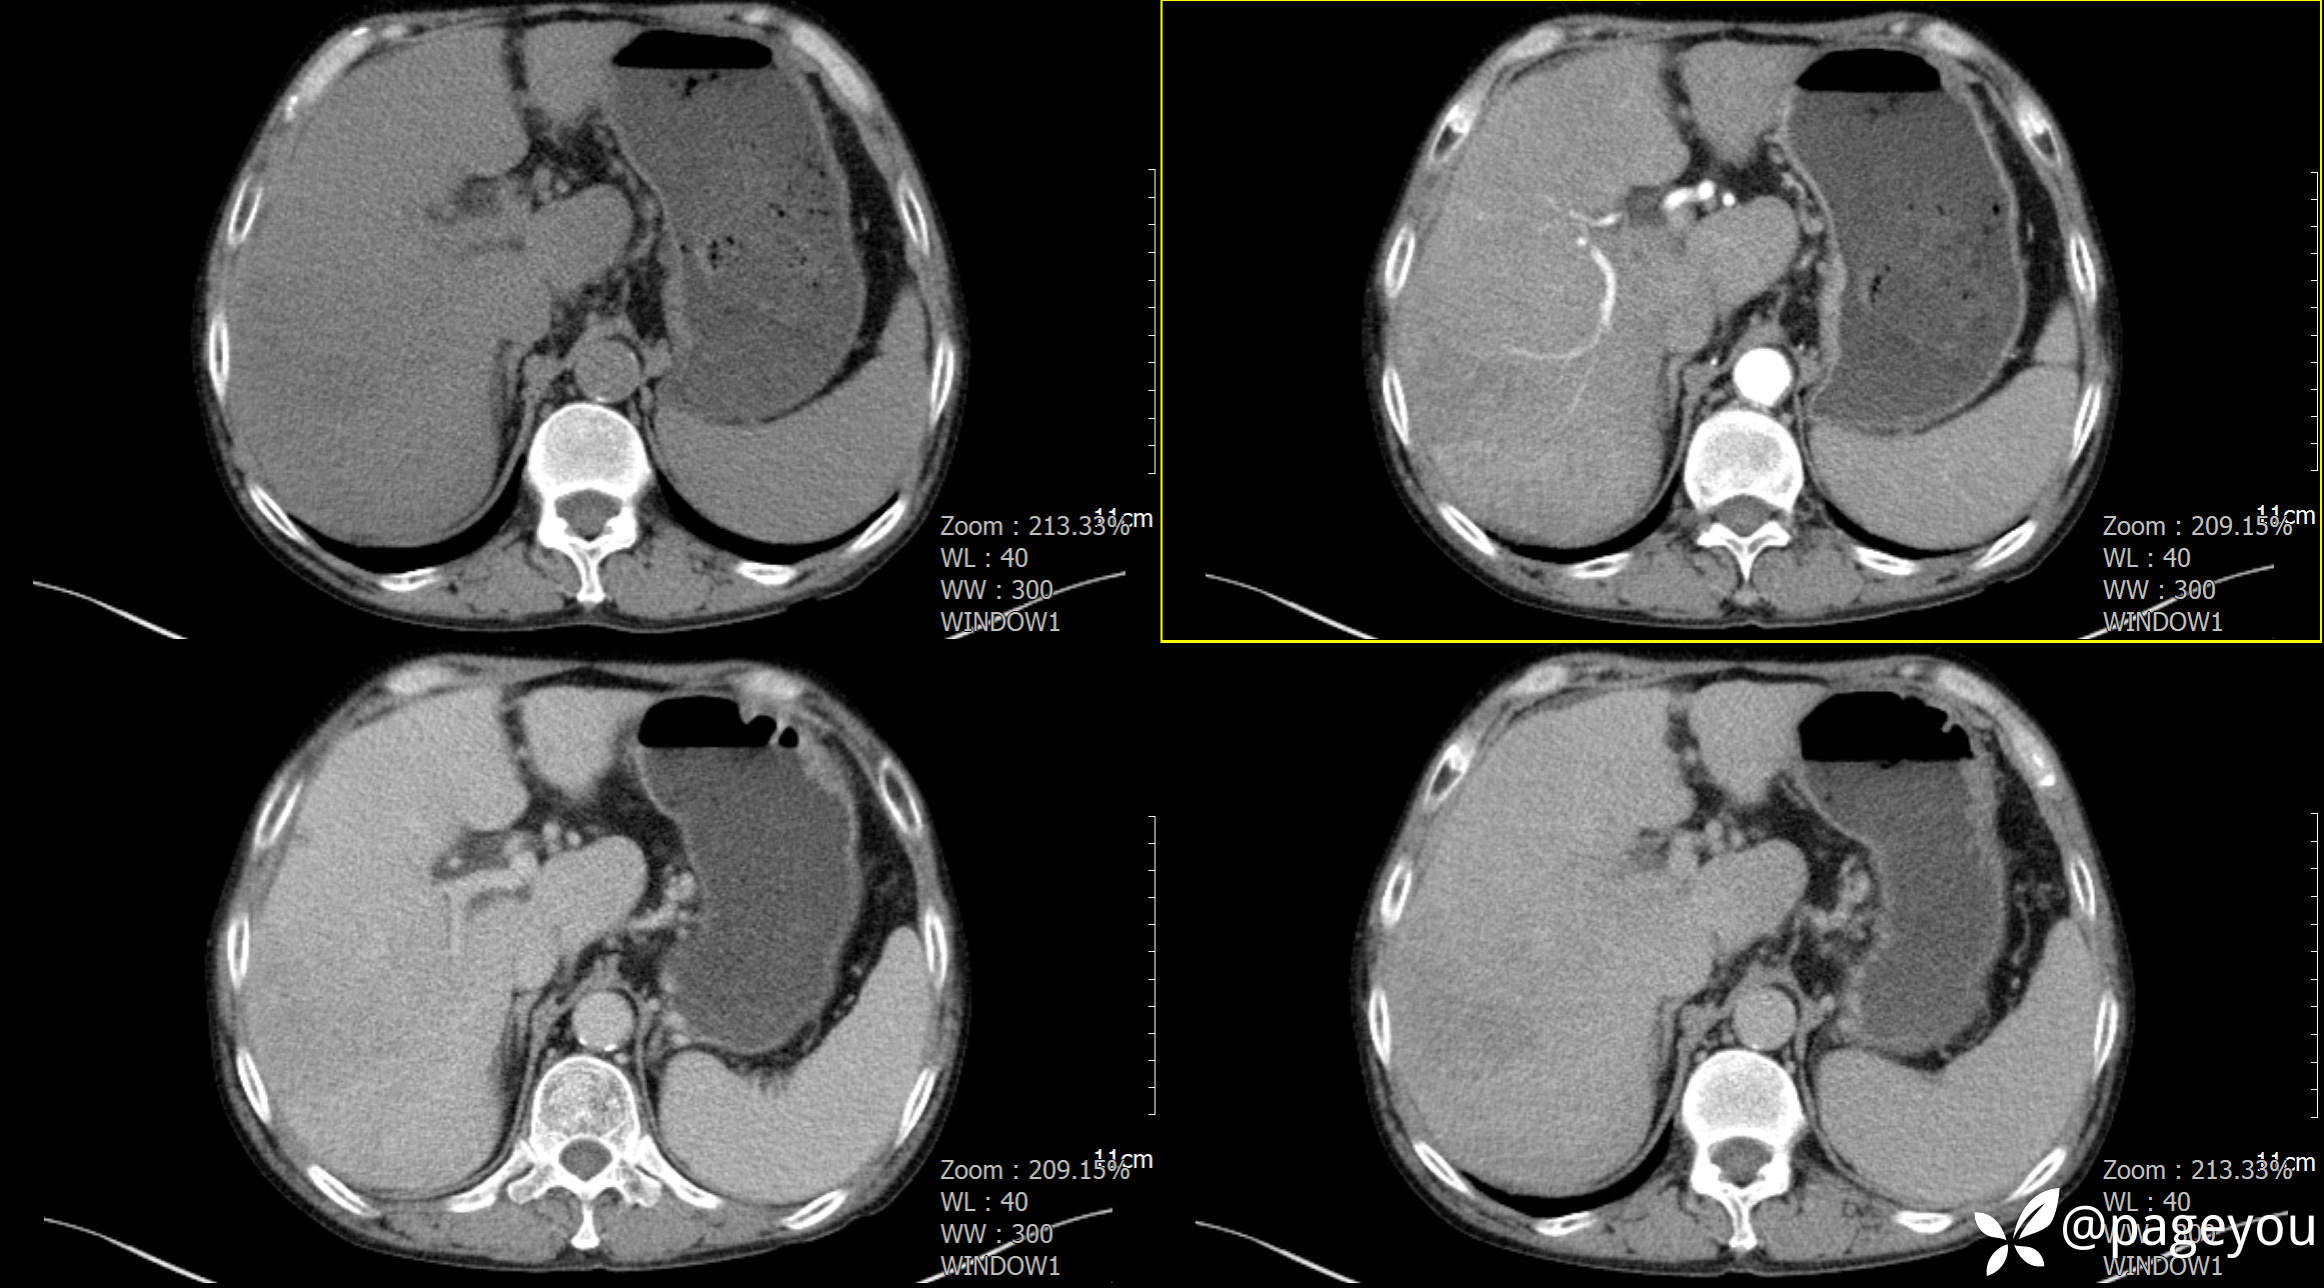

CT检查: